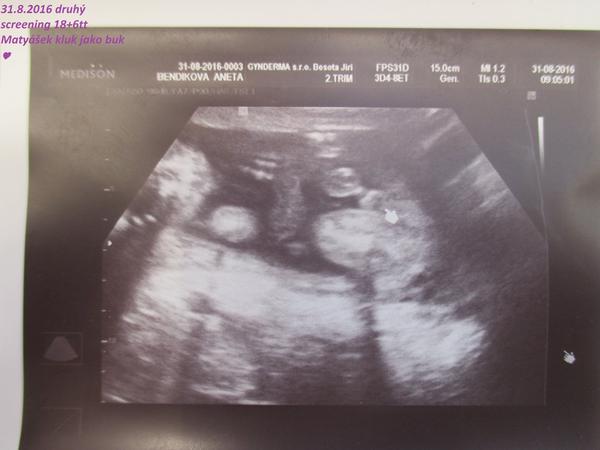

Včera mi byl chlapeček potvrzen, takže holky neumíme 🙂.